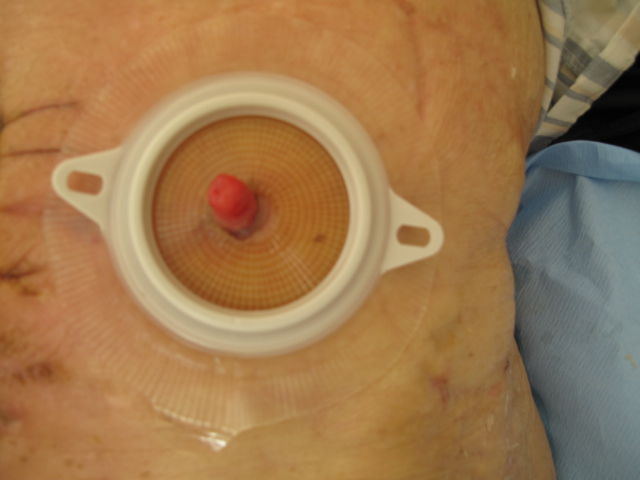

术后一个月,输尿管形成乳头(此为84岁高龄、哮喘、膀胱全切术后患者)

双侧输尿管乳头形成